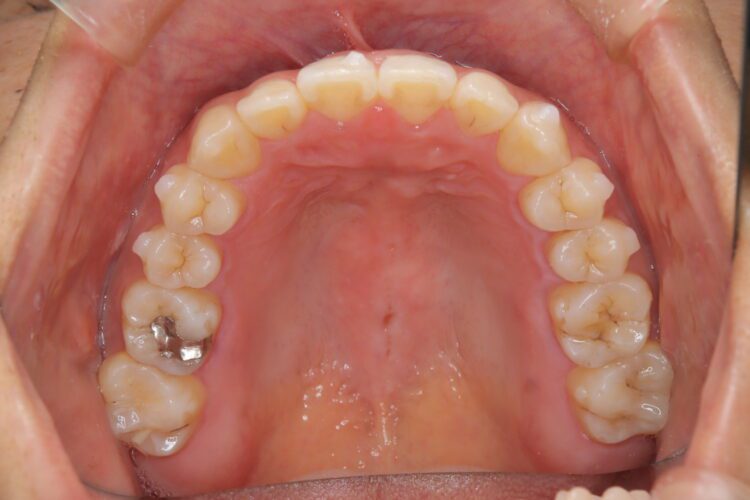

受け口の改善を主訴にご来院された患者様です。

軽度の下顎前突と診断し、マウスピース矯正装置(インビザライン)を用いて治療を行うこととしました。

治療の際はゴム掛けが必要になりましたが、患者様が非常に真面目に使用してくださったおかげで、スムーズに治療が進みました。途中の海外赴任という大きな予定変更がありましたが、そのご努力の甲斐あって、無事に渡航前に矯正を完了することができました。